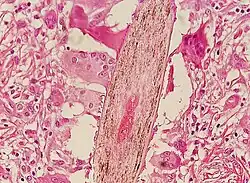

Chronic folliculitis surrounding central sebaceous hyperplasia, right mid-chest

Chronic folliculitis surrounding central sebaceous hyperplasia, right mid-chest